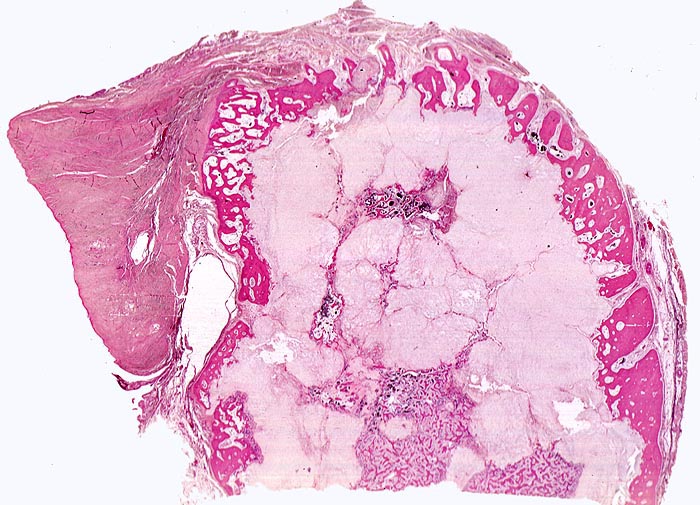

Morphologische Merkmale:

• Von Periost bedeckter kortikaler Knochen.

• Zellarmer lobulierter Knorpeltumor.

• Destruktive Tumorinfiltration des spongiösen und kortikalen Knochens.

• Der maligne Knorpel mit reichlich heller chondroider Matrix gleicht nicht neoplastischem hyalinem Knorpelgewebe.

• Im Vergleich zu normalem Knorpel leicht erhöhte Zellularität.

• In Höhlen liegende Tumorzellen mit hyperchromatischen, leicht vergrösserten Kernen.